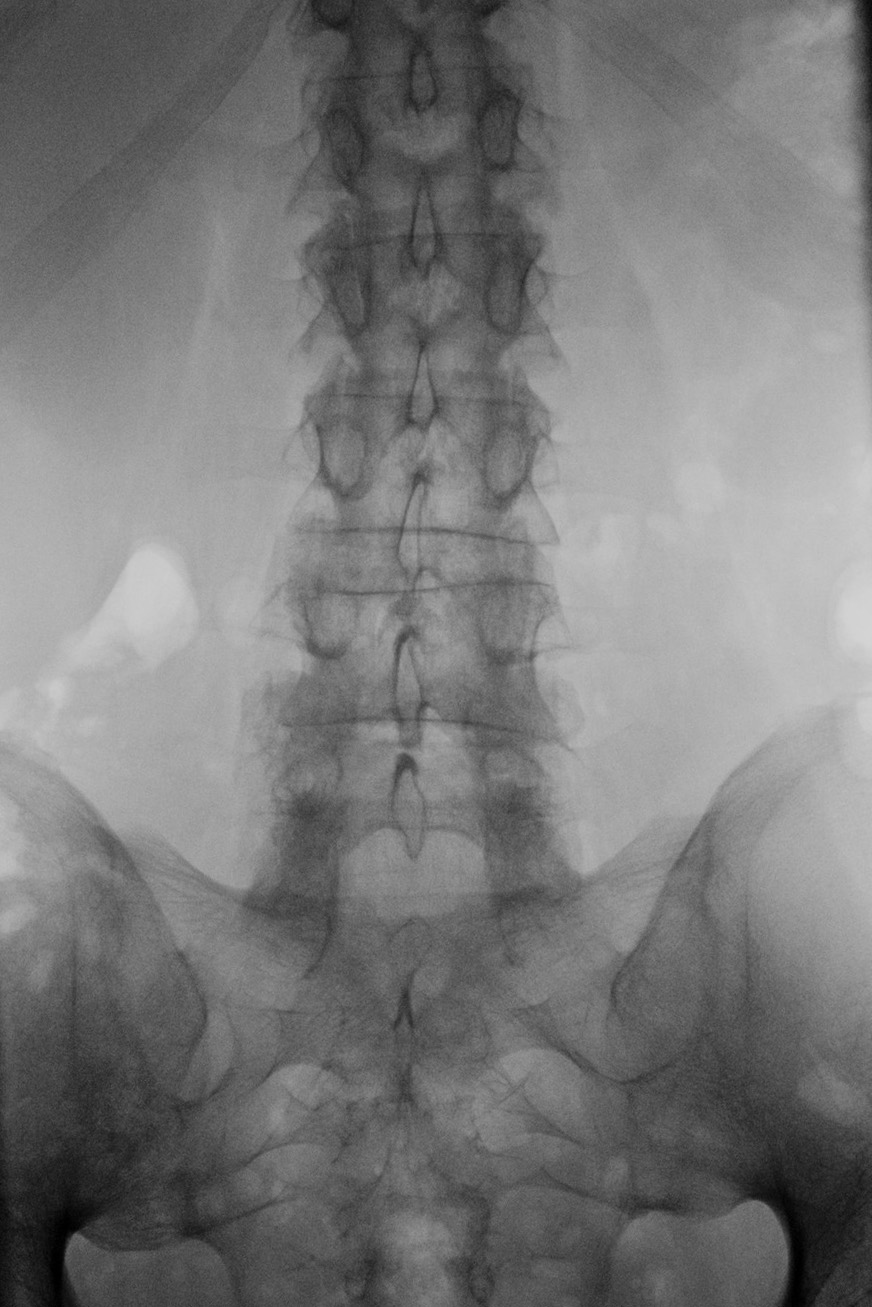

Allerdings zeigten sich schon recht bald nach dem Wechsel, dass 14 Tage dann wohl doch zu lange sind, um den Bechterew vollständig in Schach zu halten. Gegen Ende der jeweiligen Zeitphase bekomme ich neuerdings wieder die ganz klassischen Bechterew-Probleme im Hüftbereich. Die ich schon seit vielen Jahren nicht mehr hatte bzw. nicht mehr wahrgenommen habe, da die anderen durch die Entzündungen ausgelösten Probleme viel deutlicher und drängender waren. Nachdem diese aber ja in den vergangenen Monaten alle geheilt sind, merke ich nun den Beginn neuer Entzündungen recht deutlich. Und die treten dort zutage, wo die Bechterew-Entzündungen klassischer Weise nunmal meistens losgehen. Im Bereich der unteren LWS (Lendenwirbelsäule). Damit einhergehend oder eher dadurch begründet erlebe ich das als eine Art Flashback in längst vergangene und auch verdrängte Zeiten: ich wache gegen Ende der Nacht wieder früher auf, da es keine Position gibt, in der man noch beschwerdefrei liegen könnte. Meine Bewegungsfähigkeit ist die ersten Minuten nach dem Aufstehen wieder etwas eingeschränkt und ich habe meine Wärmflaschen wiederbelebt, da Wärme nach wie vor sehr gut gegen die Schmerzen hilft. Und ich komme mir allgemein ein Bisschen unbeweglicher vor als noch vor Wochen, das kann allerdings auch täuschen. Andererseits verflüchtigen sich all diese Probleme durch genügend Bewegung und ich musste (von einer Ausnahme abgesehen) auch nach wie vor nicht wieder zu Schmerzmitteln greifen. Dennoch: Im Körper passiert wieder etwas.